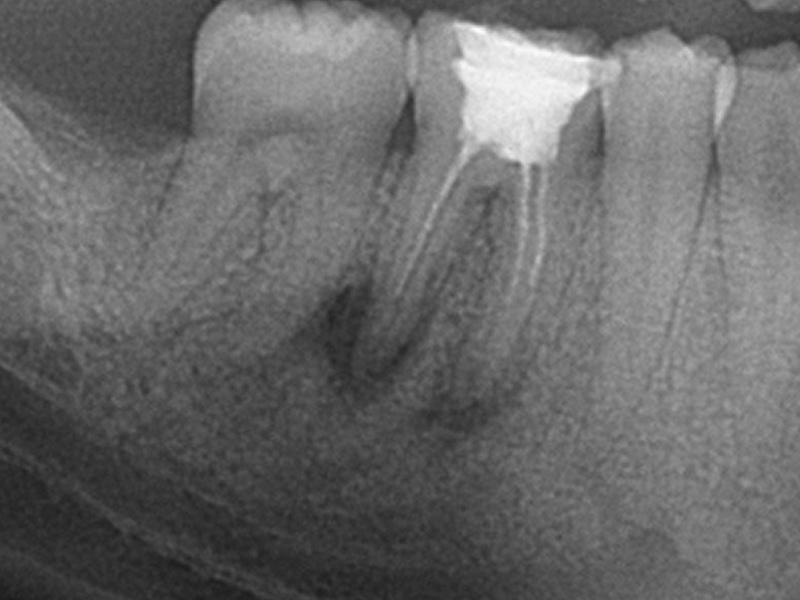

The success of the endodontic treatment should be checked with an X-ray of the tooth. Ultimately, the tooth should be restored with a filling, post, or crown to ensure proper function and aesthetics.